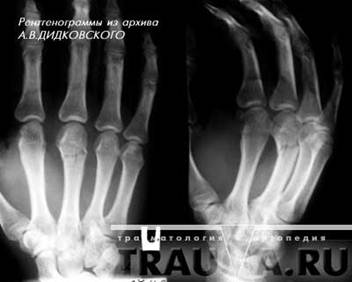

Переломы второй, третьей, четвертой и пятой пястных костей встречаются несколько реже. Возникают они под воздейтвием прямой травмы кисти и реже при ударе кулаком или при падении на кулак. Часто возникают переломы не одной, а нескольких пястных костей. Смещение отломков может быть незначительным, так как пястные кости фиксированы одна к другой связками и мышцами. Но чаще, особенно при множественных переломах, отломки смещаются по длине под углом, открытым в ладонную или тыльную стороны кисти. Пациент жалуется на боли в кисти, ладони, усиливающиеся при попытке сжать кисть в кулак. Для определения места перелома пациента тянут за палец, при переломе соответствующей пястной кости, боль резко усиливается. Диагноз уточняют при помощи рентгеновских снимков(рис.4) (17, с.145).

Рисунок 4 - Перелом головки 3 пястной кости с небольшим смещением, в двух проекциях